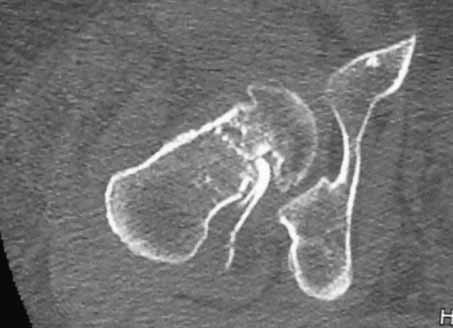

Пациентка 53 лет. ДТП 09.01.12: сочетанная травма: перелом 2-5 ребер справа, ушиб легких; перелом обеих лонных костей без смещения; закрытый перелом проксимального конца правой бедренной кости; открытый оскольчатый внутрисуставной перелом проксимальных концов костей правой голени.

В нашей клинике 11.01 выполнен минимально инвазивный остеосинтез большеберцовой кости (снимки до операции не перефотографировал) с пластикой перемещенными лоскутами дефекта, образовавшегося вследствие некроза кожи на передней поверхности голени. Бедро одномоментно делать не стал, не было уверенности в наличии перелома на уровне шейки. Во время операции смотрел тазобедренный сустав под ЭОПом, головка неподвижна. После операции повторили КТ, стало очевидно, что имеется субкапитальный перелом.

И еще: не явится ли препятствием для введения гвоздя дугообразный изгиб диафиза бедренной кости? Вершина деформации расположена на 110мм дистальнее проксимального края малого вертела. Это я по КТ измерил точно. Можно, конечно, думать о короткой ножке. Но обеспечит ли она достаточную фиксацию при таком переломе?